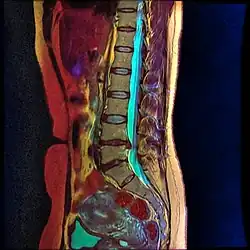

Desiccation of the L4-L5 and L5-S1 spinal discs are evident on color MRI as loss of blue color is visible on these levels.